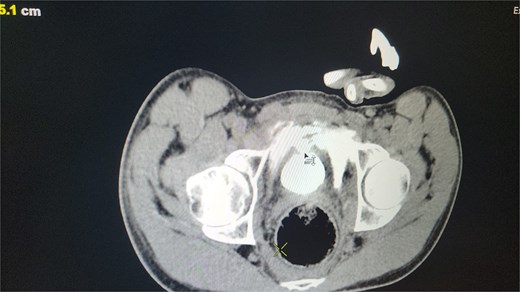

All seven cases of bladder rupture both spontaneous and traumatic were treated surgically via exploratory laparotomy to repair the injury (see Fig. 2). In both types of cases, the ruptured bladder was successfully closed (see Fig. 3). Postoperatively, Redon drain was removed on the second day, and a urinary catheter was maintained for 3 weeks to aid healing.

The image shows an extraperitoneal bladder rupture, revealing a tear in the bladder wall and damage to surrounding tissues.